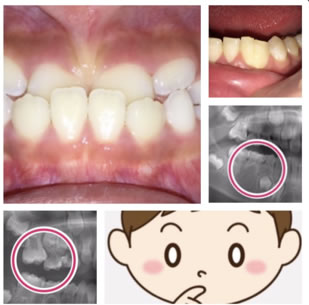

6歳臼歯(第一大臼歯)が手前の乳歯にひっかかっている状態。

奥歯が手前の乳臼歯にひっかかり、きちんと生えてこれない状態です。専門的には、第一大臼歯の「異所萌出」と言います。

上の6歳臼歯に多く、右左どちらかにだけ認められることが多いです。

① 乳臼歯が大きい

② 乳臼歯の後ろ、あるいは6歳臼歯の手前の形が膨らんでいる

③ 上顎歯列の幅が狭い

そのままにすると、6歳臼歯がさらに前に傾いて噛み合わせが悪くなります。また、虫歯になってしまう事があります。

引っかかる原因の乳臼歯を抜くと、6歳臼歯は前に寄りながら萌出してしまうので、抜いた乳臼歯の下にある永久歯が萌出するスペースが無くなってしまいます。

ブラケットを装着して、6歳臼歯を後ろに移動させ、萌出させる事です。状態によっては、他の方法もあります。

手間の乳臼歯は、根が溶けて吸収しているので、早く抜けてしまう事が多いです。そのような場合、せっかく良い位置に移動させた6歳臼歯が、再び手間に倒れてきてしまうので、保隙装置を装着する必要があります。

6歳臼歯の放出遅延をそのままにするとさらに前に傾いて

噛み合わせが悪くなります。

また、虫歯になってしまう事があります。

引っかかる原因の乳臼歯を抜くと、6歳臼歯は前に寄りながら萌出してしまうので、

抜いた乳臼歯の下にある永久歯が萌出するスペースが無くなってしまいます。